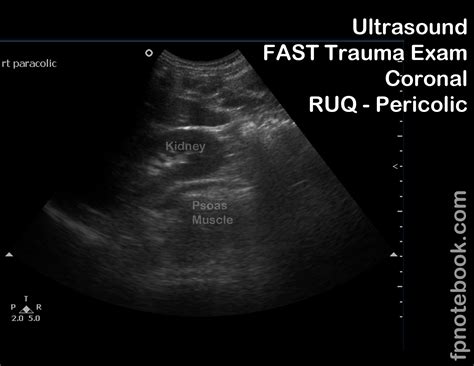

• EFAST (Extended Focused Assessment with Sonography for Trauma): This is a comprehensive ultrasound examination used to evaluate patients with trauma. It includes views of the heart, lungs, abdomen, and pelvis to detect fluid collections, pneumothorax, and other injuries.

• Trauma Assessment: In trauma patients, the Fast Exam Ultrasound helps identify internal injuries, such as hemoperitoneum, hemothorax, and pericardial effusion.